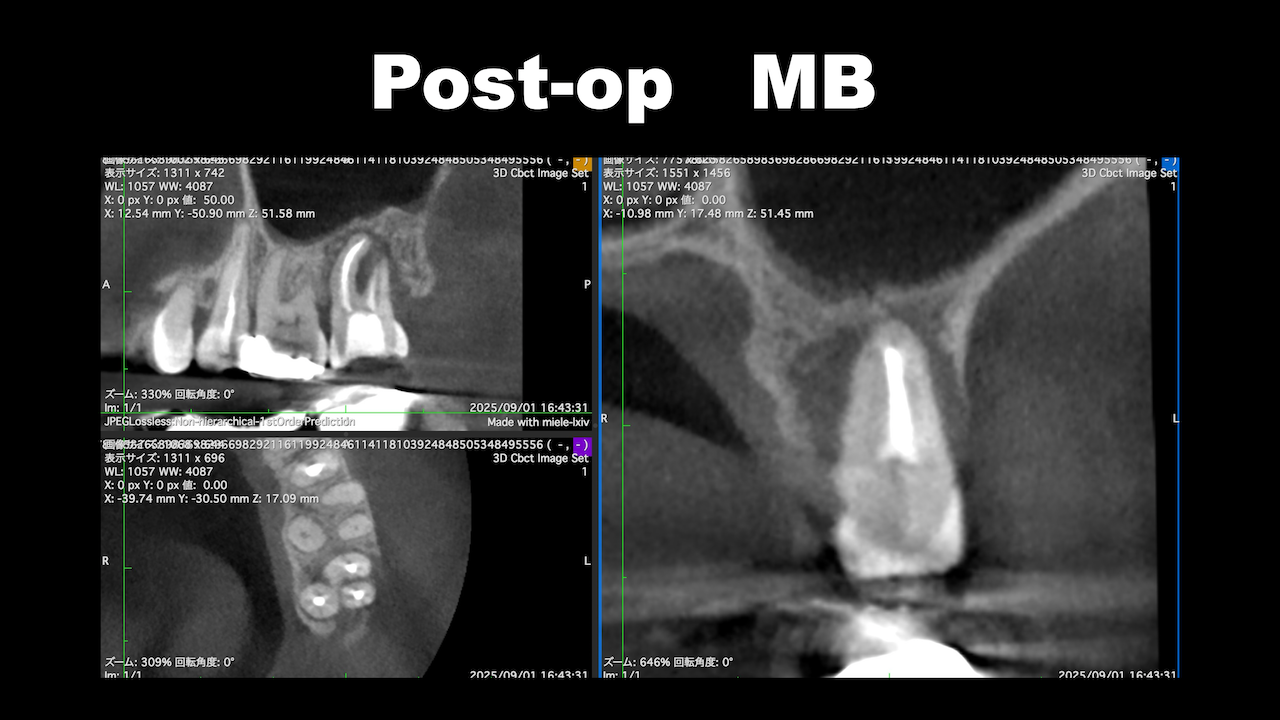

術後にCBCTを撮影するが、

問題はない。